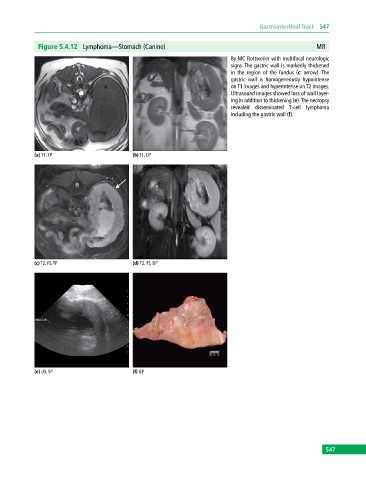

Figure 5.4.12 Lymphoma—Stomach (Canine) MR

8y MC Rottweiler with multifocal neurologic

signs. The gastric wall is markedly thickened

in the region of the fundus (c: arrow). The

gastric wall is homogeneously hypointense

on T1 images and hyperintense on T2 images.

Ultrasound images showed loss of wall layer-

ing in addition to thickening (e). The necropsy

revealed disseminated T‐cell lymphoma

including the gastric wall (f).

(a) T1, TP (b) T1, DP

(c) T2, FS, TP (d) T2, FS, DP

(e) US, SP (f) GP